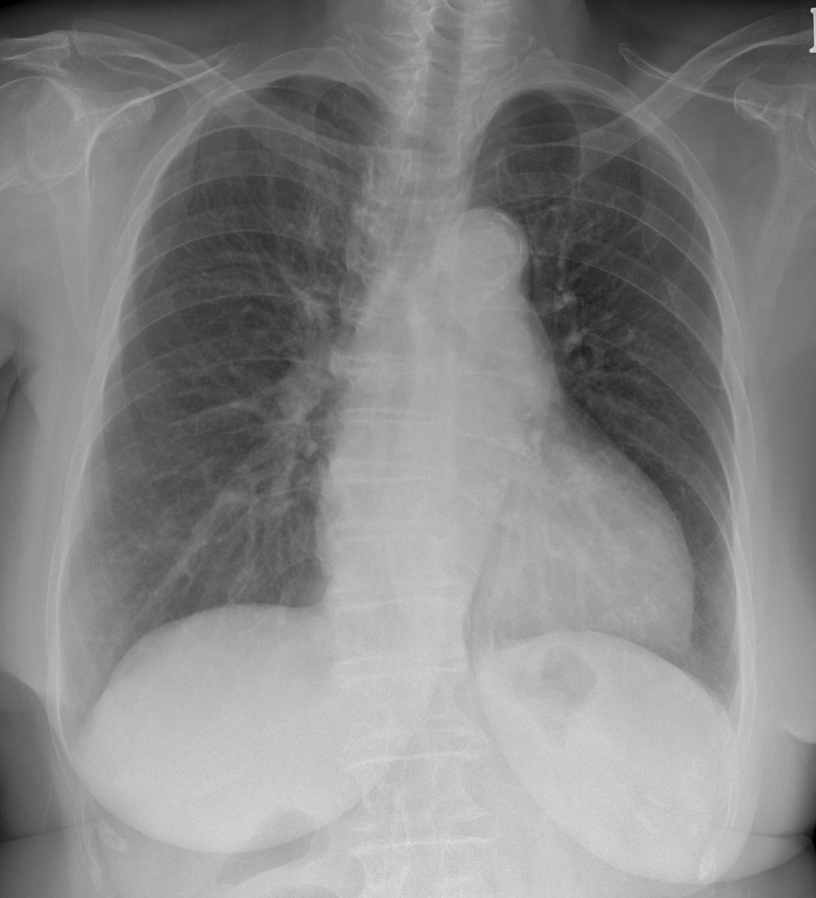

Relevant Test Results Prior to Catheterization

Baseline investigations confirmed preserved renal function (creatinine 1.03 mg/dL) with no acute deterioration. Transthoracic echocardiography (TTE) demonstrated moderate aortic stenosis with preserved left ventricular systolic function (LVEF 63%), relevant both prognostically and in guiding hemodynamic management during the procedure. The rest of her laboratory results were insignificant. The resting ECG was reviewed in the context of the patient¡¯s known long QT history and showed normal sinus rhythm with heart rate of 86 beats per minute and a left bundle branch block. Her medications were carefully reconciled prior to admission and dual antiplatelet therapy was confirmed as ongoing. No contrast allergy was documented.